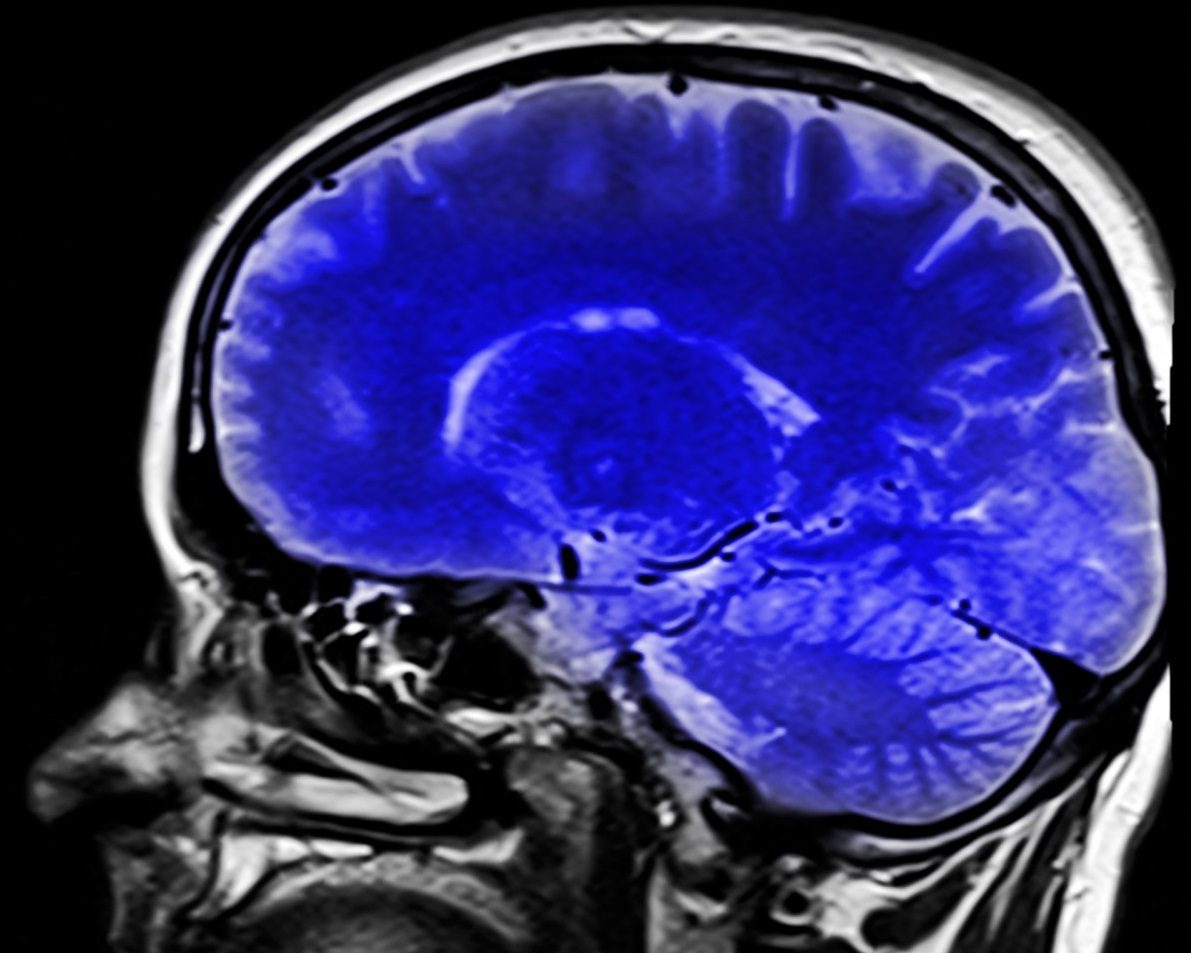

En este contexto, cabe recordar que la enfermedad de Alzheimer, descrita por primera vez en 1906 por el neurólogo y psiquiatra alemán Aloysius Alois Alzheimer, constituye el tipo más común –en torno a un 50-75% del total de casos– de demencia, así como que a día de hoy conviven en todo el mundo en torno a 50 millones de personas con demencia. Además, de acuerdo con las estimaciones de los especialistas, la cifra total de pacientes con demencia se duplicará cada 20 años.